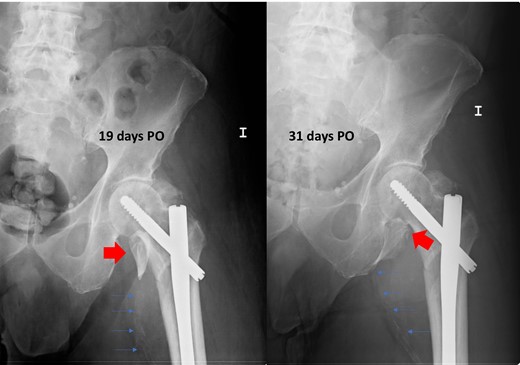

Postoperative radiographs after intertrochanteric fracture synthesis with trochanteric nail 19 and 31 days after surgery. Secondary displacement of LT can be observed (wide arrows) and of the calcified femoral vessels (thin arrows), indirect signs of the presence of a pseudoaneurysm.

We present a case of an 80-year-old institutionalized man, who suffered an unstable intertrochanteric fracture of the left hip, type 31.A2.1 (AO-OTA) due to a low energy accident after falling from his own height. The patient previous medical history included bipolar disorder, hypertension, DM, and right inguinal herniorrhaphy surgery. The patient underwent closed reduction and internal fixation with an intramedullary nail type Gamma3 (Stryker Trauma GmbH Prof. Küntscher-Str. 1-5 24 232 Schönkirchen, Germany) of the fracture during the first 24 hours after injury. The surgical procedure was performed without any intraoperative complications. He was discharged from the hospital on the sixth postoperative day, asymptomatic, with a postoperative hematoma in the left thigh, walking with a walking frame, with a postoperative radiographic control showing a correct nail placement without alterations and with an hemoglobin value (HGB) of 10.7 g/dl and a hematocrit value (HCT) of 30.8%. On the 18th postoperative day, he suffered a fall after having a syncopal episode, so he went to the emergency room and was admitted to the hospital for study. The hematoma in his thigh was evolving correctly, and the radiographs remained unchanged with respect to the previous ones. He was discharged two days later. One month after surgery, he returned to the hospital due to persistent pain, volume increase and progressive hematoma in the left thigh. The blood analysis showed an anemia (HGB 9.5 g/dL, HCT 29%). The pedia pulse was present and the posterior tibial pulse was weaker than the contralateral but also present. An X-ray showed a superior and medial displacement of the lesser trochanter compared to previous radiographs and a medialization of the femoral artery, visible because it was calcified (Fig. 1). A Doppler ultrasound was performed showing a hypoechoic lesion with turbulent flow inside compatible with pseudoaneurysm at the level of the deep femoral artery or one of its branches. The study was completed with a CT angiography that confirmed the presence of a pseudoaneurysm of 7.3 × 6.7 × 6 cm at the level of the deep femoral artery at the beginning of the lateral circumflex branch (Fig. 2). At that time, the patient was referred to the Interventional Radiology Service. The vascular lesion was immediately treated by femoral transcatheter embolization with two distal coils in the lateral circumflex artery measuring 3 and 4 mm (Axium 3D Medtronic 9775 Toledo Way Irvine, CA 92 618 USA) and proximal embolization by a liquid embolic agent, Onyx 34 (Covidien 106-108 Rue la Boetie 75 008 Paris, France).